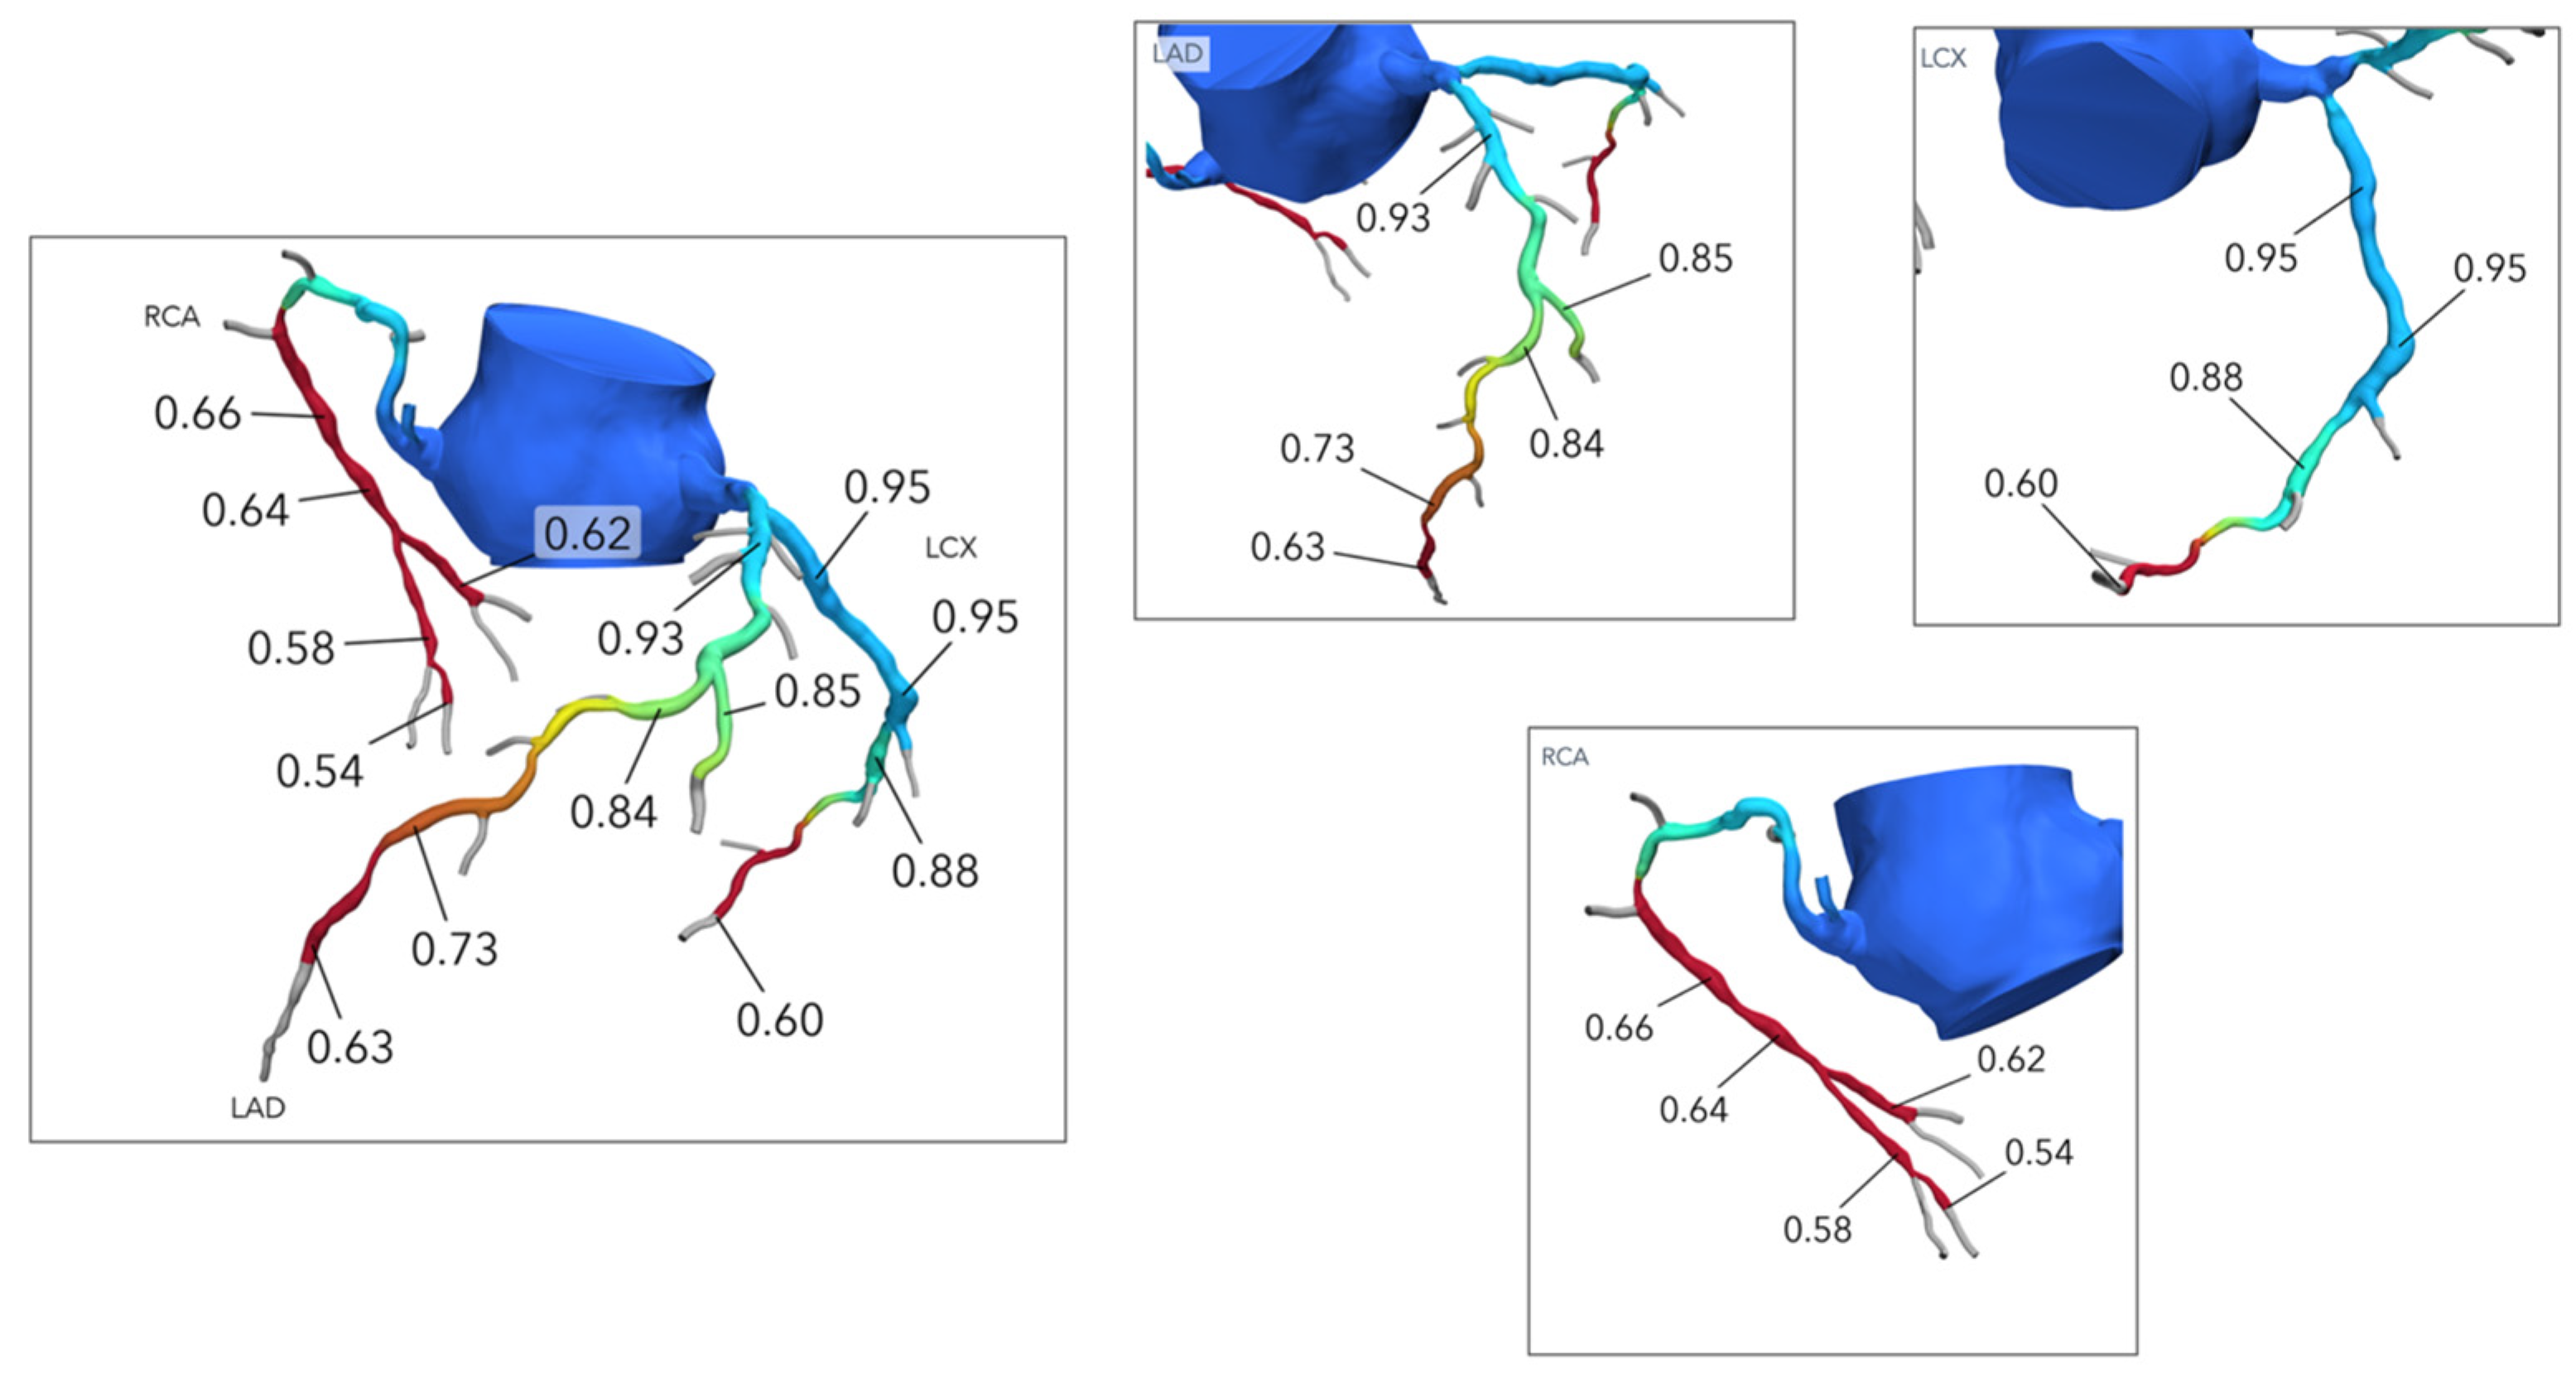

3. Coronary Plaque Assessment

4. Functional Evaluation of Coronary Stenoses

5. Cardiac Computed Tomography-Derived Coronary Artery Volume to Myocardial Mass